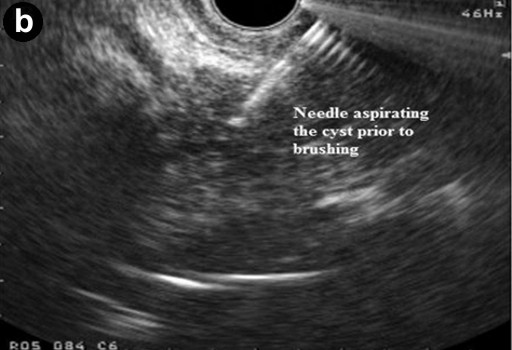

All patients had platelet count and coagulation profile checked and corrected if needed prior to the procedure. Procedures were done under intravenous sedation with diazepam and pethidine or midazolam and fentanyl. Cyst sampling was done by two operators with a combined experience of over 1,000 linear EUS procedures (GPA and KR). The lesion was identified and punctured using a 19 G needle using curvilinear echoendoscope (GF-UCT240-AL5, Olympus KeyMed, Essex, United Kingdom) and 50% of the cyst content was initially aspirated. The echobrush (Cook Medical, Limerick, Ireland, United Kingdom) was then passed through the handle and advanced through the needle till the whole brush could be visualised in the cyst. The wall of the cyst was then brushed by to and fro movement of the brush tip by moving the shaft of the needle at the handle. The opposite wall of the cyst was then visualised by moving the handle of the scope sideways and the brushing repeated at least four times (Figure 1). The brush was targeted if septae or nodules were present on the cyst wall. The brush was pulled back into the needle tip prior to removing the needle from the cyst and the needle apparatus with echobrush was withdrawn as a whole. The cyst was then aspirated to dryness using either a 19 G or 22 G needle. In patients where only FNA was done the cyst was punctured and aspirated using a 22 G needle.

Figure 1. Linear endoscopic ultrasound showing EUS-guided brushing of a cystic pancreatic lesion. a. EUS-FNA 19 G needle entering a cystic lesion in the head of the pancreas. b. The cyst being aspirated. c. The cyst wall being brushed by echobrush introduced through the needle. d. The cyst aspirated to dryness after cyst wall brushing. |